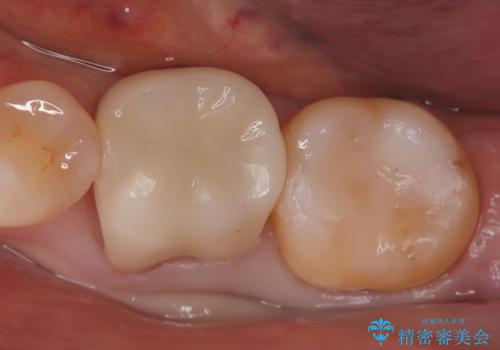

治療では、まず虫歯に侵された歯質を丁寧に除去し、セラミッククラウンを装着するための歯の形成を行いました。型取りから患者様の歯の形や色に合わせたオーダーメイドのセラミッククラウンを作製。セラミックは、隣接する歯との隙間なく精密に適合し、プラークが付着しにくいため、虫歯の再発を防ぐ効果があります。最終的に、精度の高いクラウンを装着し、咬み合わせを細かく調整しました。これにより、虫歯の再発を防ぎ、快適に食事ができる奥歯を取り戻していただけました。